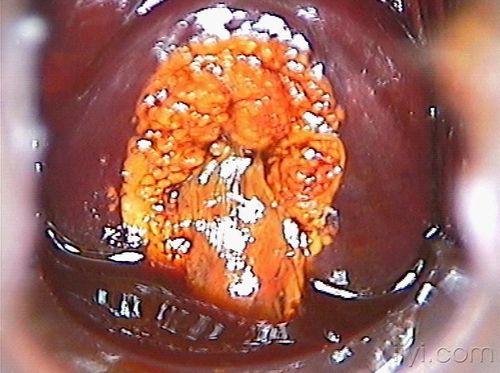

子宫糜烂图片1到3度,宫颈糜烂高清照片图片

临床常见宫颈糜烂图片

宫颈糜烂高清照片图片

宫颈糜烂图片1到3度